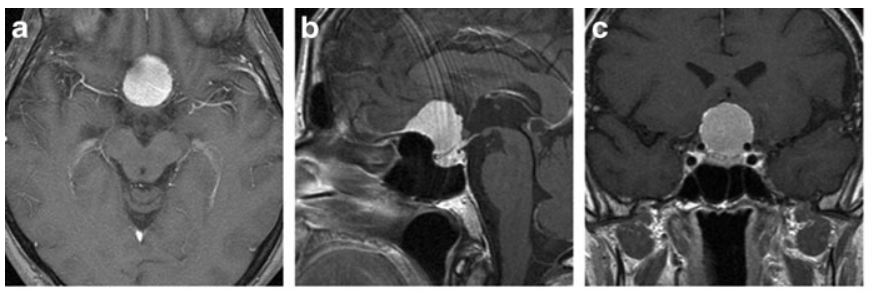

a–c 术前增强T1加权MRI,均显示鞍结节脑膜瘤